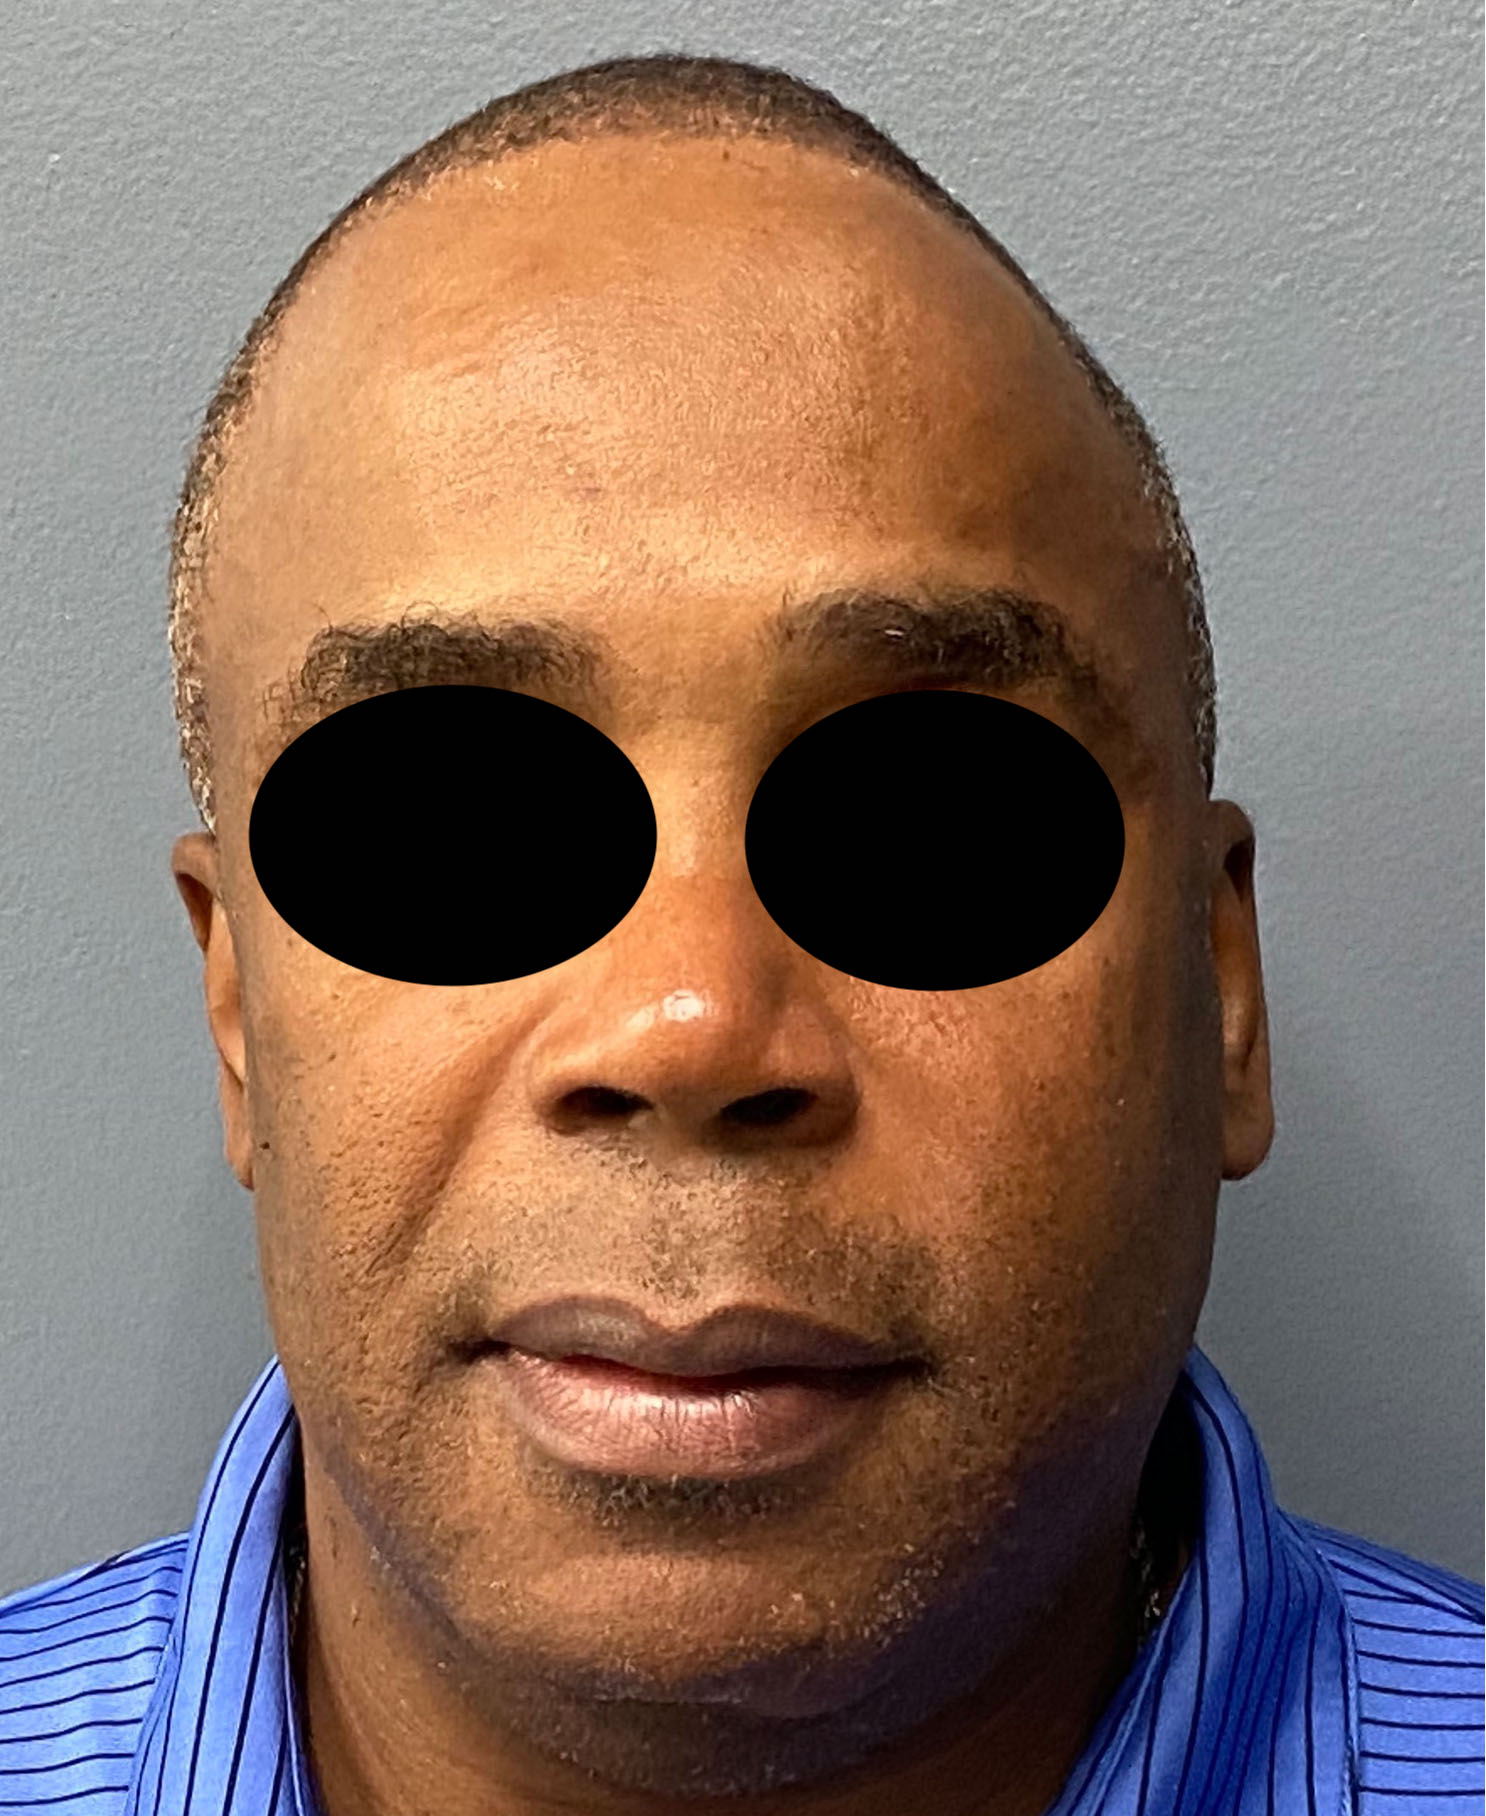

Patient 84

Desire for change of head shape from front view form an inverted V shape to a rounder and wider head shape.

Placement of custom extended forehead-temporal implants through incisions in the crease behind the ear. (he had a prior back of head skull implant which is green in the implant designs and which the head widening implants partially covered it)

Desire for change of head shape from front view form an inverted V shape to a rounder and wider head shape.

Placement of custom extended forehead-temporal implants through incisions in the crease behind the ear. (he had a prior back of head skull implant which is green in the implant designs and which the head widening implants partially covered it)